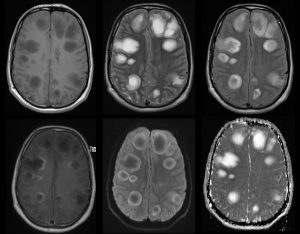

- RM T1 axial B. RM T2 axial C. RM FLAIR axial D. RM T1 axial con contraste E y F. RM DIFUSIÓN axial

Múltiples lesiones redondeadas hemisféricas bilaterales cortico-subcorticales y subcorticales, la mayoría de gran tamaño y distribución asimétrica. Se presentan hipointensas en secuencias T1 e hiperintensas en T2 y FLAIR (con periferia más hiperintensa en T1 y más hipointensa en T2). No restringen en secuencia difusión (*) y presentan realce tras la administración de contraste en forma de anillo, algunas de ellas incompleto y abierto hacia la sustancia gris (flecha).